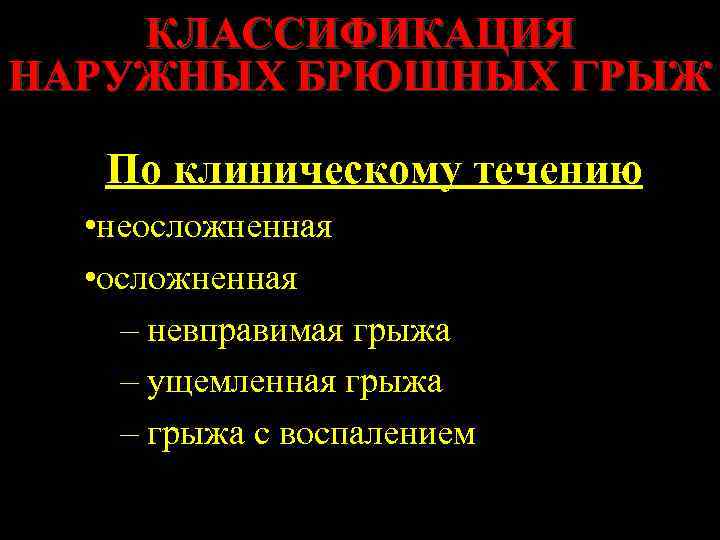

КЛАССИФИКАЦИЯ НАРУЖНЫХ БРЮШНЫХ ГРЫЖ По клиническому течению • неосложненная • осложненная – невправимая грыжа – ущемленная грыжа – грыжа с воспалением